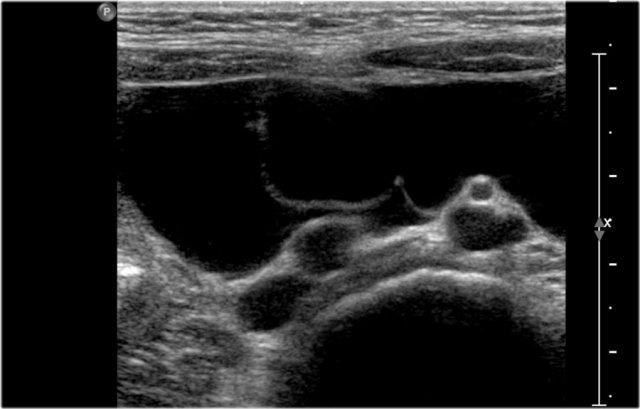

Đây là hình ảnh một nang được phát hiện trước sinh, được xác nhận sau khi sinh ở một bé gái sơ sinh.

Quan sát thấy một nang có mức dịch-dịch (fluid-fluid level).

Trong phẫu thuật, phát hiện xoắn buồng trứng trái.